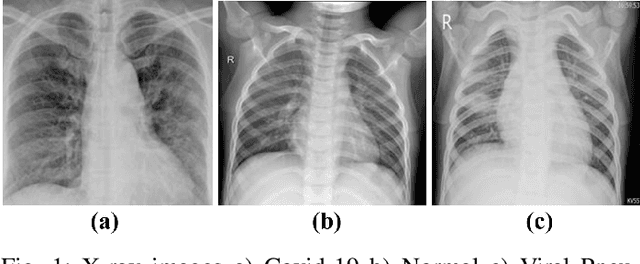

Abstract:The new coronavirus 2019, also known as COVID19, is a very serious epidemic that has killed thousands or even millions of people since December 2019. It was defined as a pandemic by the world health organization in March 2020. It is stated that this virus is usually transmitted by droplets caused by sneezing or coughing, or by touching infected surfaces. The presence of the virus is detected by real-time reverse transcriptase polymerase chain reaction (rRT-PCR) tests with the help of a swab taken from the nose or throat. In addition, X-ray and CT imaging methods are also used to support this method. Since it is known that the accuracy sensitivity in rRT-PCR test is low, auxiliary diagnostic methods have a very important place. Computer-aided diagnosis and detection systems are developed especially with the help of X-ray and CT images. Studies on the detection of COVID19 in the literature are increasing day by day. In this study, the effect of different batch size (BH=3, 10, 20, 30, 40, and 50) parameter values on their performance in detecting COVID19 and other classes was investigated using data belonging to 4 different (Viral Pneumonia, COVID19, Normal, Bacterial Pneumonia) classes. The study was carried out using a pre-trained ResNet50 convolutional neural network. According to the obtained results, they performed closely on the training and test data. However, it was observed that the steady state in the test data was delayed as the batch size value increased. The highest COVID19 detection was 95.17% for BH = 3, while the overall accuracy value was 97.97% with BH = 20. According to the findings, it can be said that the batch size value does not affect the overall performance significantly, but the increase in the batch size value delays obtaining stable results.

Abstract:Covid-19 is a very serious deadly disease that has been announced as a pandemic by the world health organization (WHO). The whole world is working with all its might to end Covid-19 pandemic, which puts countries in serious health and economic problems, as soon as possible. The most important of these is to correctly identify those who get the Covid-19. Methods and approaches to support the reverse transcription polymerase chain reaction (RT-PCR) test have begun to take place in the literature. In this study, chest X-ray images, which can be accessed easily and quickly, were used because the covid-19 attacked the respiratory systems. Classification performances with support vector machines have been obtained by using the features extracted with residual networks (ResNet-50), one of the convolutional neural network models, from these images. While Covid-19 detection is obtained with support vector machines (SVM)-quadratic with the highest sensitivity value of 96.35% with the 5-fold cross-validation method, the highest overall performance value has been detected with both SVM-quadratic and SVM-cubic above 99%. According to these high results, it is thought that this method, which has been studied, will help radiology specialists and reduce the rate of false detection.

Abstract:The 2019 novel coronavirus (COVID-19), with a starting point in China, has spread rapidly among people living in other countries, and is approaching approximately 305,275 cases worldwide according to the statistics of European Centre for Disease Prevention and Control. There are a limited number of COVID-19 test kits available in hospitals due to the increasing cases daily. Therefore, it is necessary to implement an automatic detection system as a quick alternative diagnosis option to prevent COVID-19 spreading among people. In this study, three different convolutional neural network based models (ResNet50, InceptionV3 and Inception-ResNetV2) have been proposed for the detection of coronavirus pneumonia infected patient using chest X-ray radiographs. ROC analyses and confusion matrices by these three models are given and analyzed using 5-fold cross validation. Considering the performance results obtained, it is seen that the pre-trained ResNet50 model provides the highest classification performance with 98% accuracy among other two proposed models (97% accuracy for InceptionV3 and 87% accuracy for Inception-ResNetV2).